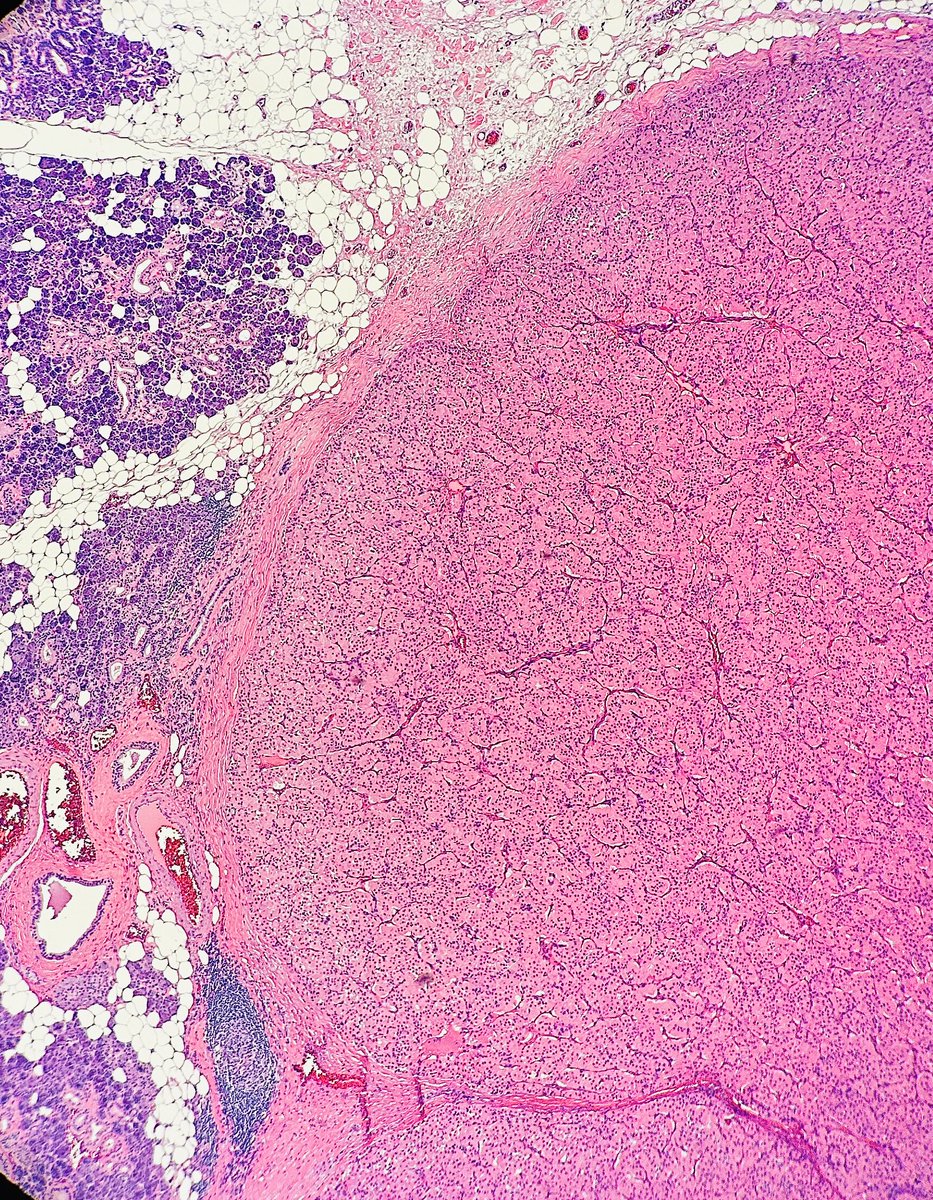

Tristan Rutland MBBS FRCPA IFCAP@TristanRutland7·

🔬𝐓𝐫𝐢𝐩𝐥𝐞-𝐍𝐞𝐠𝐚𝐭𝐢𝐯𝐞 𝐁𝐫𝐞𝐚𝐬𝐭 𝐂𝐚𝐫𝐜𝐢𝐧𝐨𝐦𝐚 (𝐍𝐒𝐓) 🔬 ⚠️ Pitfall alert 1️⃣ TNBCs can exhibit a range of morphologies, from metaplastic (sometimes resembling salivary gland tissue) to poorly differentiated or undifferentiated forms. 2️⃣ DCIS is usually absent. 3️⃣ GATA3 may be lost 4️⃣ SOX10 is usually positive (mimic melanoma). 5️⃣ 𝐃𝐢𝐚𝐠𝐧𝐨𝐬𝐭𝐢𝐜 𝐓𝐢𝐩: Always do a keratin and review patients history! #Breastpath #Dermpath #Pathtwitter #Pathresidents

Tristan Rutland MBBS FRCPA IFCAP tweet mediaTristan Rutland MBBS FRCPA IFCAP tweet mediaTristan Rutland MBBS FRCPA IFCAP tweet mediaTristan Rutland MBBS FRCPA IFCAP tweet media